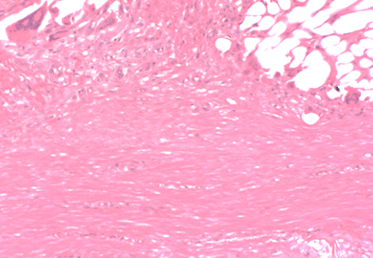

The BioBrace® Implant Filled With New Tissue

Oriented New Tissue Generation: The advanced 3D structure of BioBrace® provides internal channels that naturally guide alignment of new fibers.

Rapid Cellular Infiltration: The highly porous scaffold provides the ideal environment for cell infiltration and proliferation to form new, functional tissue.